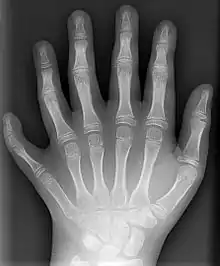

قام وليام رونتجن، مكتشف الأشعة السينية، بتسليط شعاع إلكتروني داخل أنبوب زجاجي مطبق بين طرفيه توتر كهربائي مرتفع. كان هذا الأنبوب مفرغ من الهواء وتنطلق بداخله إلكترونات من قطب كهربائي سالب إلى قطب كهربائي موجب. تم إحاطة هذا الإنبوب بورق ذو لون فاتح لحماية المستخدم من المجال الكهرمغناطيسي المنبعث. تم وضع شاشة فسفورية في نهاية الإنبوب. عندما اصطدام الشعاع الإلكتروني بها، بدأت هذه الشاشة بالتوهج. عندما وضع ريتشارد رونتجن يده بالصدفة بين الأنبوب والشاشة الفسفورية، شاهد صورة لعظام يده على الشاشة، وكانت هذه أول عملية تصوير بالأشعة السينية.[1]

- التصوير الشعاعي في الطب للكشف عن الأسنان والعظام وكسورها وتحديد مواقع الأجسام الصلبة مثل الشظايا أو الرصاص في الجسم، وكذلك الكشف عن الأورام في الجسم، بفضل هذه الأشعة أصبح من الممكن رؤية الكسور العظمية بدقة عالية حيث تستطيع هذه الأشعة اختراق الأجسام اللينة مثل الجلد ولكنها لا تستطيع المرور عبر العظام، مما يؤدي لظهور صورة الأخيرة. من أهم ما يميزها هو قلة أضرارها الجانبية .